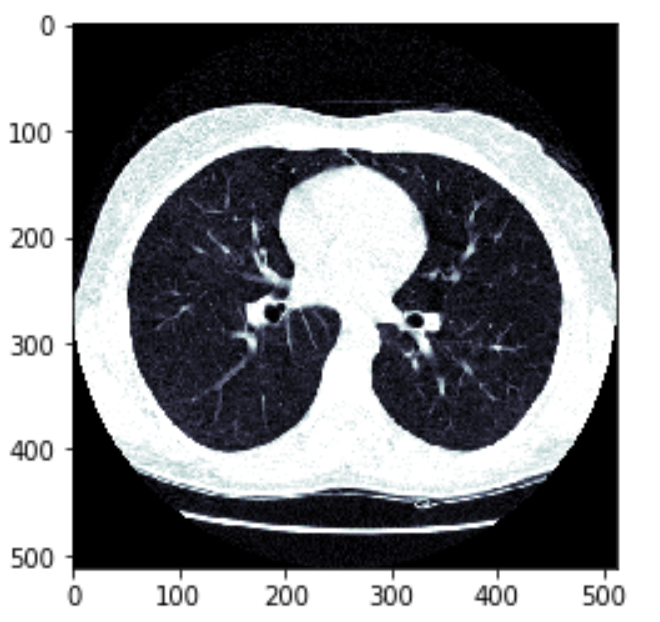

显示下肺窗下的图像:

img_norm_arr = sitk.GetArrayFromImage(img_norm)

plt.imshow(img_norm_arr[68], cmap='bone')